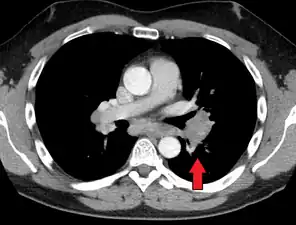

Hilar adenopathy especially on the person's left (AP CXR)

Hilar adenopathy especially on the person's left (AP CXR) Hilar adenopathy especially on the person's left (lateral CXR)

Hilar adenopathy especially on the person's left (lateral CXR) Hilar adenopathy especially on the person's left (coronal CT)

Hilar adenopathy especially on the person's left (coronal CT) Hilar adenopathy especially on the person's left (transverse CT)

Hilar adenopathy especially on the person's left (transverse CT)